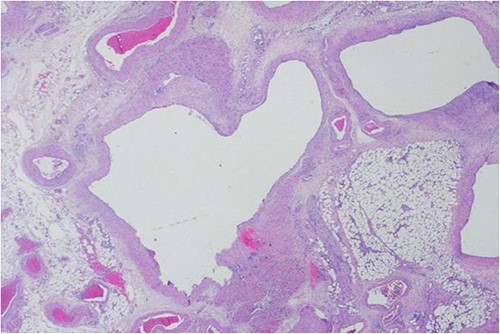

A 40-year-old Saudi, nulliparous woman, medically free with a history of leiomyoma (uterine fibroid) underwent myomectomy. She was referred to our center as a case of large abdominopelvic mass, tense ascites and pleural effusion. The patient complained of the shortness of breath, palpitation, marked abdominal discomfort and bloating as well as back pain. She reported that she first noticed the bloating 3 months prior to the visit. However, she was unable to come because of COVID-19 pandemic situation. She is a housewife; never smoked tobacco or drank alcohol, and had no history of recent travel to endemic or pandemic areas. On further investigations, a serum CA-125 was found to be elevated 492.6 U/mL (normal < 35 U/mL), whereas the concentration of other tumor markers LDH, CEA, CA19-9 and ALP was within normal ranges. Abdominal CT scan revealed a significant interval increase in the size of ascites, which caused a huge abdominal distention along with severe mass effects on the abdominopelvic organs, which have been displaced posteriorly as shown in Fig. 1. In addition, it revealed a large exophytic uterine fibroid measuring 15 × 20 × 17.5 cm. A therapeutic paracentesis was done with the removal of 50.750 ml of ascitic fluid. Figure 2 shows how pleural effusion is markedly significant. A total abdominal hysterectomy, with bilateral salpingo-oophorectomy and omentectomy, was performed. Intraoperative finding revealed a very large mass, which originated from uterine fundus. The pleural effusion and ascites disappeared entirely after the excision of abdominopelvic mass. She recovered completely and went through an uneventful postoperative period. On pathology of surgical specimens, a giant uterine leiomyoma with degenerative changes, pleural and ascitic fluids was yielded negative for malignancy and diagnosed as a benign mesothelial proliferation, whereas H&E stain of the omentum excision surprisingly confirmed multiple, large and irregular disorganized veins (thin-walled blood vessels) and arteries (thick-walled blood vessels), some with organized thrombi consistent with omental AVM as shown in Figs 3 and 4. Provisional diagnosis of pseudo-Meigs’ syndrome with omental AVM was considered.

H&E stain of the omentum excision shows multiple, large and irregular disorganized veins and arteries.